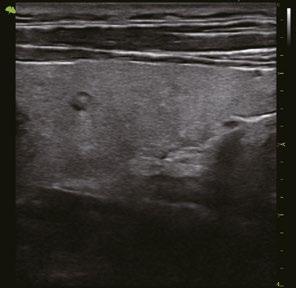

Intelligente Erfassung und Stadieneinteilung von Schilddrüsenerkrankungen

Schilddrüsenknoten werden in Echtzeit oder auf gespeicherten Bildern erkannt, zusammen mit dem T-RADS-Kategorisierungs- und Berichtstool, wodurch die klinische Routine der Schilddrüsenultraschalluntersuchung genauer und aussagekräftiger wird.